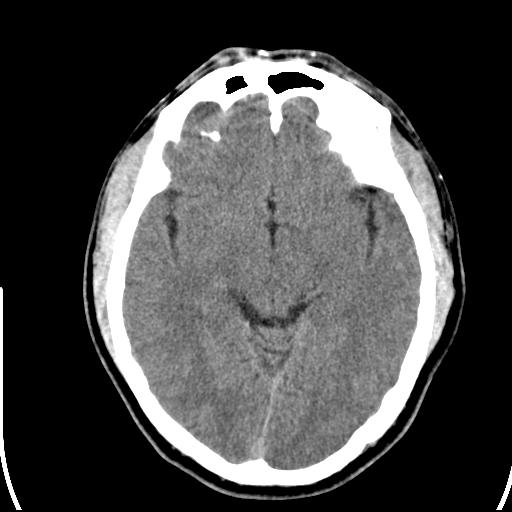

标题: CT25435:头皮下高密度影???

头皮下高密度结节影???临床上在老年男性比较常见。大家看看是什么?成因是? 本例患者,男性,51岁。外伤来诊。无染发史及发根植入史。